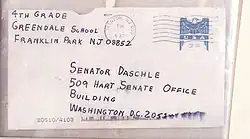

En 2001, tuvo lugar un ataque terrorista en Estados Unidos, en el cual se usaron esporas introducidas en cartas de correo. Este ataque causó 17 casos de carbunco y 5 fallecimientos.[16]